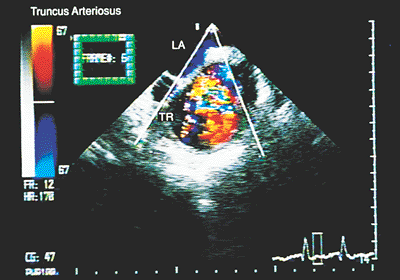

Truncus Arteriosus

When only one artery emerges from the heart, the V–A connection is defined as a single outlet. Three possibilities exist: truncus arteriosus, pulmonary atresia or aortic atresia. In truncus arteriosus, the vessel emerging from the heart originates the systemic, pulmonary, and coronary circulation. Images in the longitudinal plane obtained with a biplanar or multiplanar transducer show the truncus arteriosus straddling the interventricular septum (Fig. 8.2.57). The absence of right ventricular infundibulum is evident in transverse and longitudinal sections, and multiple images in both planes show the ventricular septal defect due to the absence of the infundibular septum. Transverse sections also show supernumerary truncal leaflets.

As the transducer is withdrawn to a plane slightly superior to the truncal valve, an attempt should be made to identify the emergence of the pulmonary artery or its branches from the posterior or lateral walls of the truncus arteriosus (Figs. 8.2.58 and 8.2.59).

Color Doppler aids in detecting stenosis or regurgitation of the truncal valve.